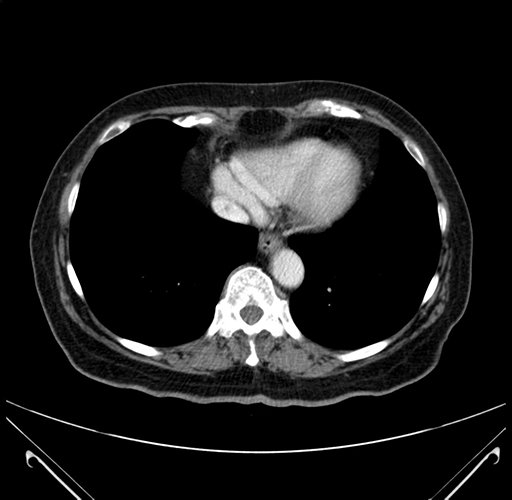

Pre-Chemo: Axial Venous